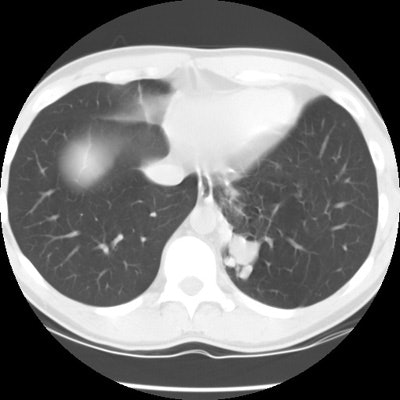

CT scan revealed a soft tissue mass in the left posterior-medial lung which had a branching tubular appearance. Some associated para-emphysematous changes were noted. (Click images to enlarge)

An arteriogram was performed and reveal a systemic arterial supply to the mass with pulmonary venous drainage. The mass was resected and determined to be an intralobar bronchopulmonary sequestration.